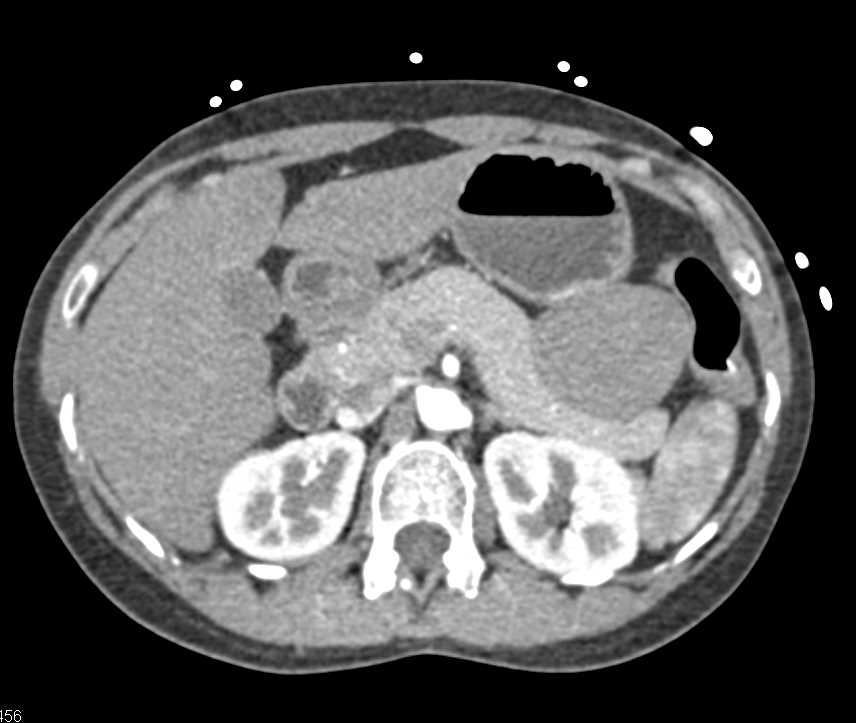

Mass Pushes on Tail of Pancreas was Ganglioneuroma